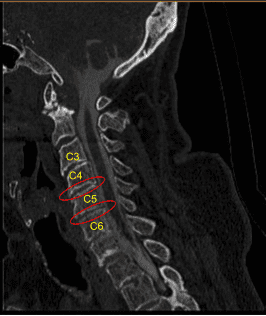

This Patient presented to the outpatient clinic with signs and symptoms of cervical spondylotic radiculopathy. Having failed extensively with nonsurgical treatments with progressively severe pain syndrome, surgery was recommended to decompress and stabilize the cervical spine.

They were positioned supine on the operating room table with the head in mild extension and the shoulders gently taped down for fluoroscopic visualization. Fluoroscopy was used to localize the C5 index level. Skin was cleaned with chlorhexidine. A transverse incision was demarcated on the right side.

Bovie monopolar was used to expose the anterior cervical spine from C4 to C6 undermining bilateral longus colli muscles. TrimLine self-retaining retractor system was placed. Caspar pins 12 mm were placed into the C4, C5 and C6 anterior vertebral bodies. Gentle retraction was applied first across C5-6.

Distraction was then applied across C4-5. Similarly, an annulotomy was performed with a #15 blade, discectomy with curettes and pituitary rongeurs, collection of autograft with Penfield, exposure of posterior longitudinal ligament with electric high-speed drill, preparation of endplates with curettes and drill, resection of PLL with nerve hook and Kerrison, bilateral neurolysis of C5 nerve roots with Penfield technique and foraminotomies with Kerrison rongeurs. Hemostasis similarly was obtained with Surgiflo hemostatic matrix, cottonoids, and thrombin soaked Gelfoam.